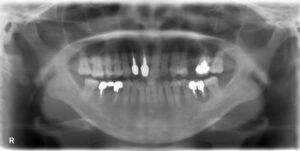

上顎前歯2本欠損症例

BEFORE AFTER 38歳男性/上2本/インプラント埋込手術 【治療内容】 左上前歯のお痛みが主訴でご来院の患者さ…